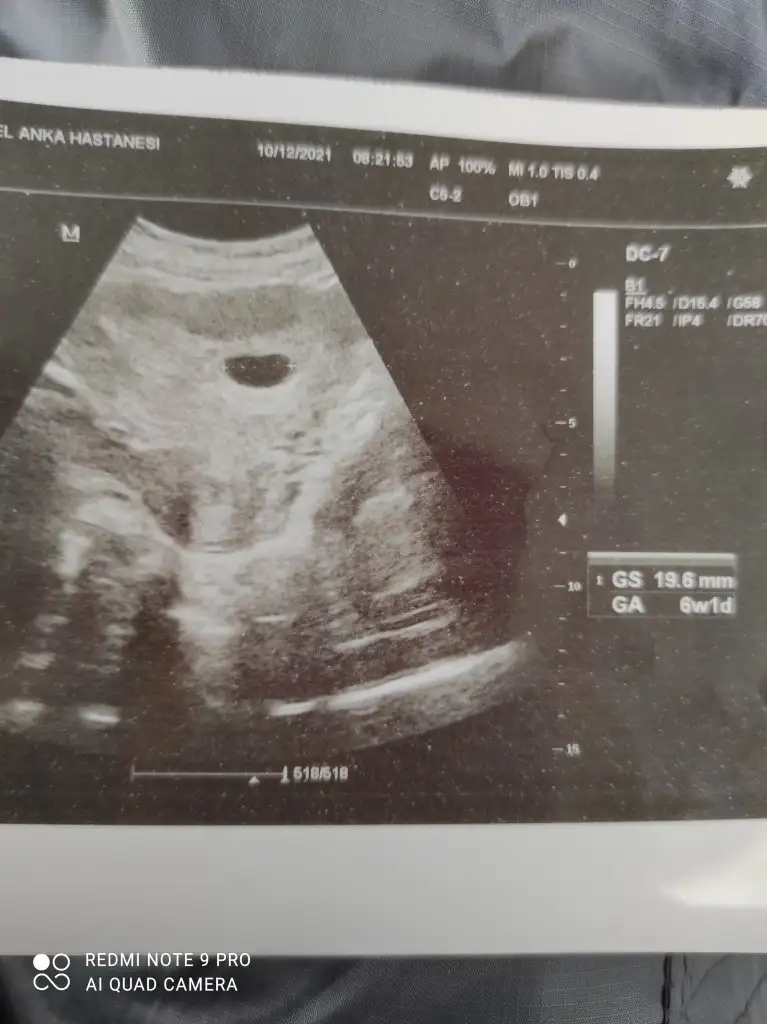

Doktordan çıktım yumurtam 12 mm mis 10 gun sonra çatlar diyor. Polikistik varmis. İlk kez duydum oylebisey. 2 tane kızı var hiç inanmadım bu doktora. Her şey aleyhime işliyor sanki. Ovulasyon yaptim ama dedim onların hepsi yalan diyor. Yumurtam şimdi 12 mm olmuşsa nasıl 10 gün durabilir ki